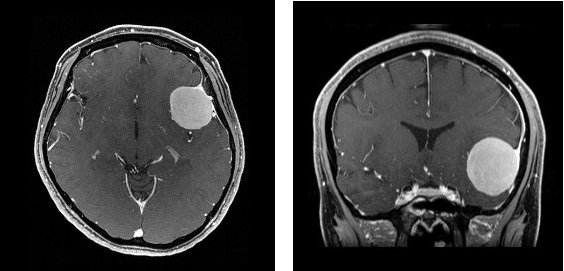

髄膜腫のMRI

髄膜腫ができる場所に応じた症状が出ます。代表的なものは頭痛や手足の動きにくさ、言葉の出にくさなどです。診断には、CTやMRIと呼ばれる脳の検査が必要です。近年では脳ドックの普及により、無症状のうちに偶然みつかることも多くなりました。